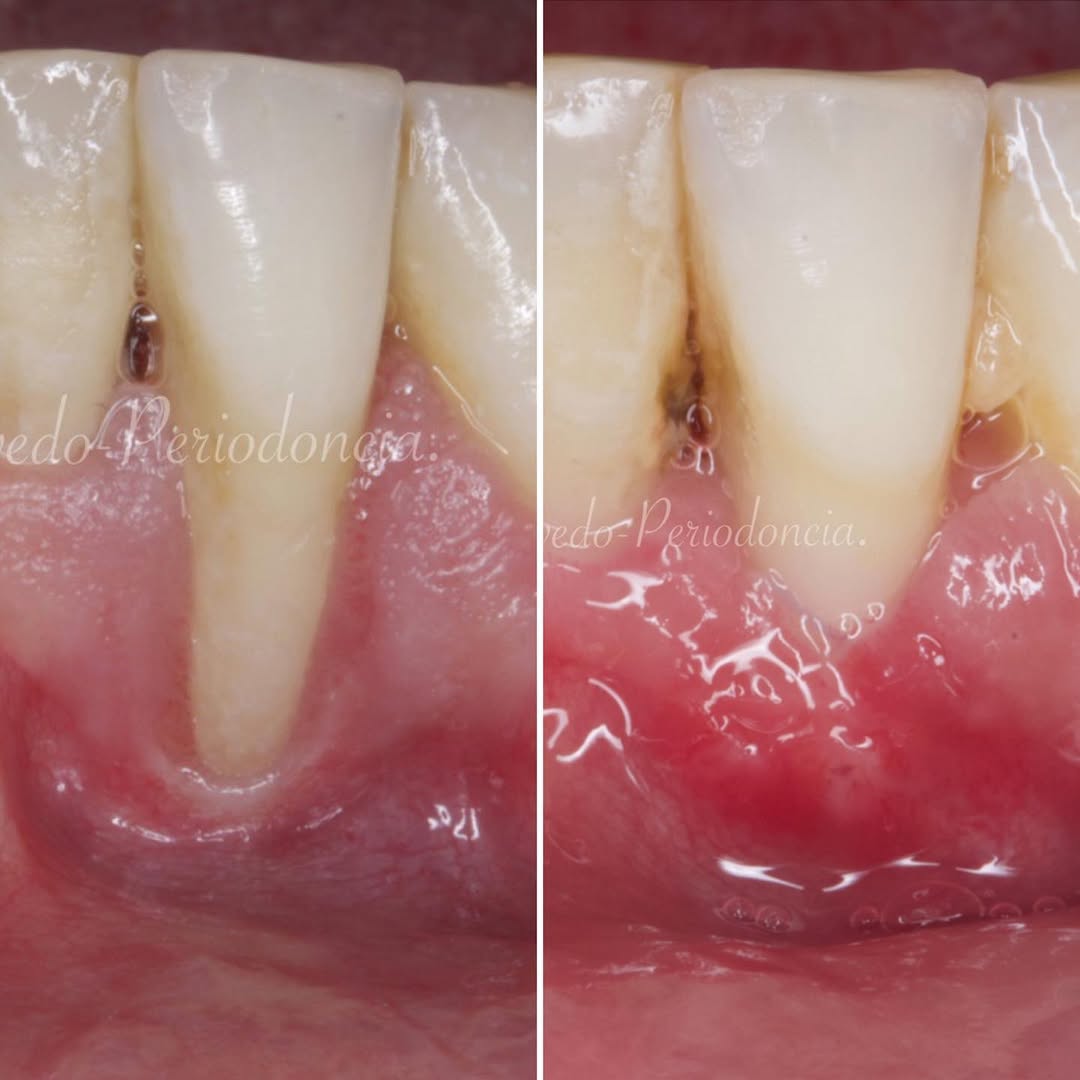

Aprende la planificación y técnica de la cirugía Mucogingival para el recubrimiento de recesiones y aumento de banda queratinizada en el sector anteroinferior

La formación comenzará con la presentación del caso clínico que se abordará durante el curso, seguida de una cirugía en directo, que permitirá observar paso a paso el procedimiento y la toma de decisiones clínicas. Durante la jornada se profundizará en los conceptos biológicos aplicados a

Durante una mañana, asistirás a una Cirugía Mucogingival de recubrimiento radicular de una recesión unitaria en 31 con frenillo asociado. Gracias al uso del microscopio y a la proyección en tiempo real en pantalla, verás exactamente lo mismo que veo yo durante la cirugía, sin tener que estar